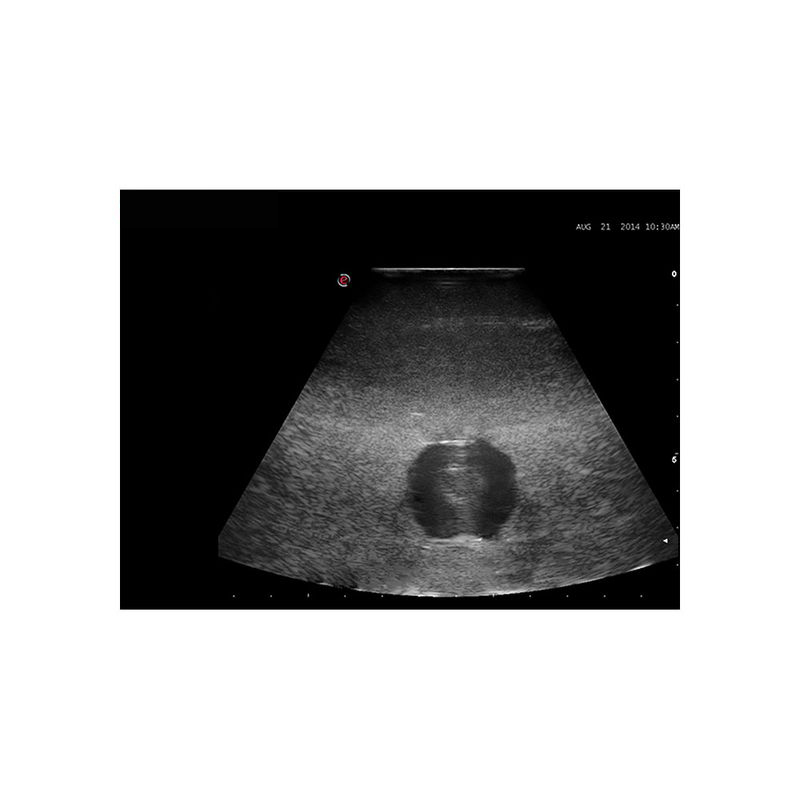

超声引导下囊肿穿刺引流模型

型号:PC-BP030

模型为培训超声引导下囊肿穿刺引流而专门设计的模型,适用于外科以及超声影像科的教学与培训。